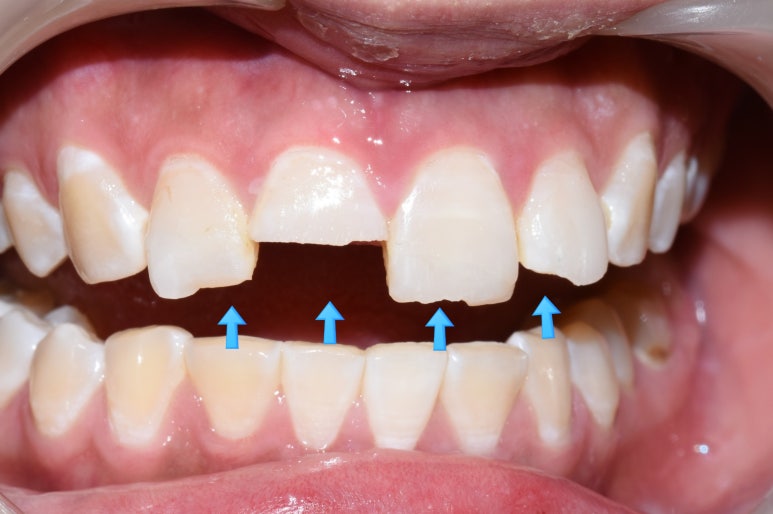

환자분이 미끄러운 곳에서 넘어지는 바람에

윗니의 앞니 4개가 깨져서 오셨습니다.

환자분 말로는 몇 달 전 한국오시기 전에 레진으로 한 번 떼운 적 있던 치아라고 하셨고

치아 하나는 아주 많이 깨져서

다른 치과에서는 발치 후 임플란트를 해야한다고 설명을 듣고 오신 치아였습니다.